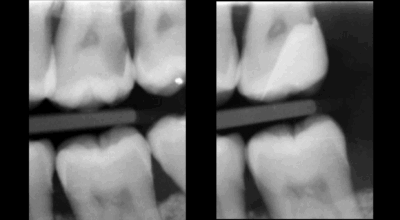

Clinical case

Root canal treatment: 80–95% success rate